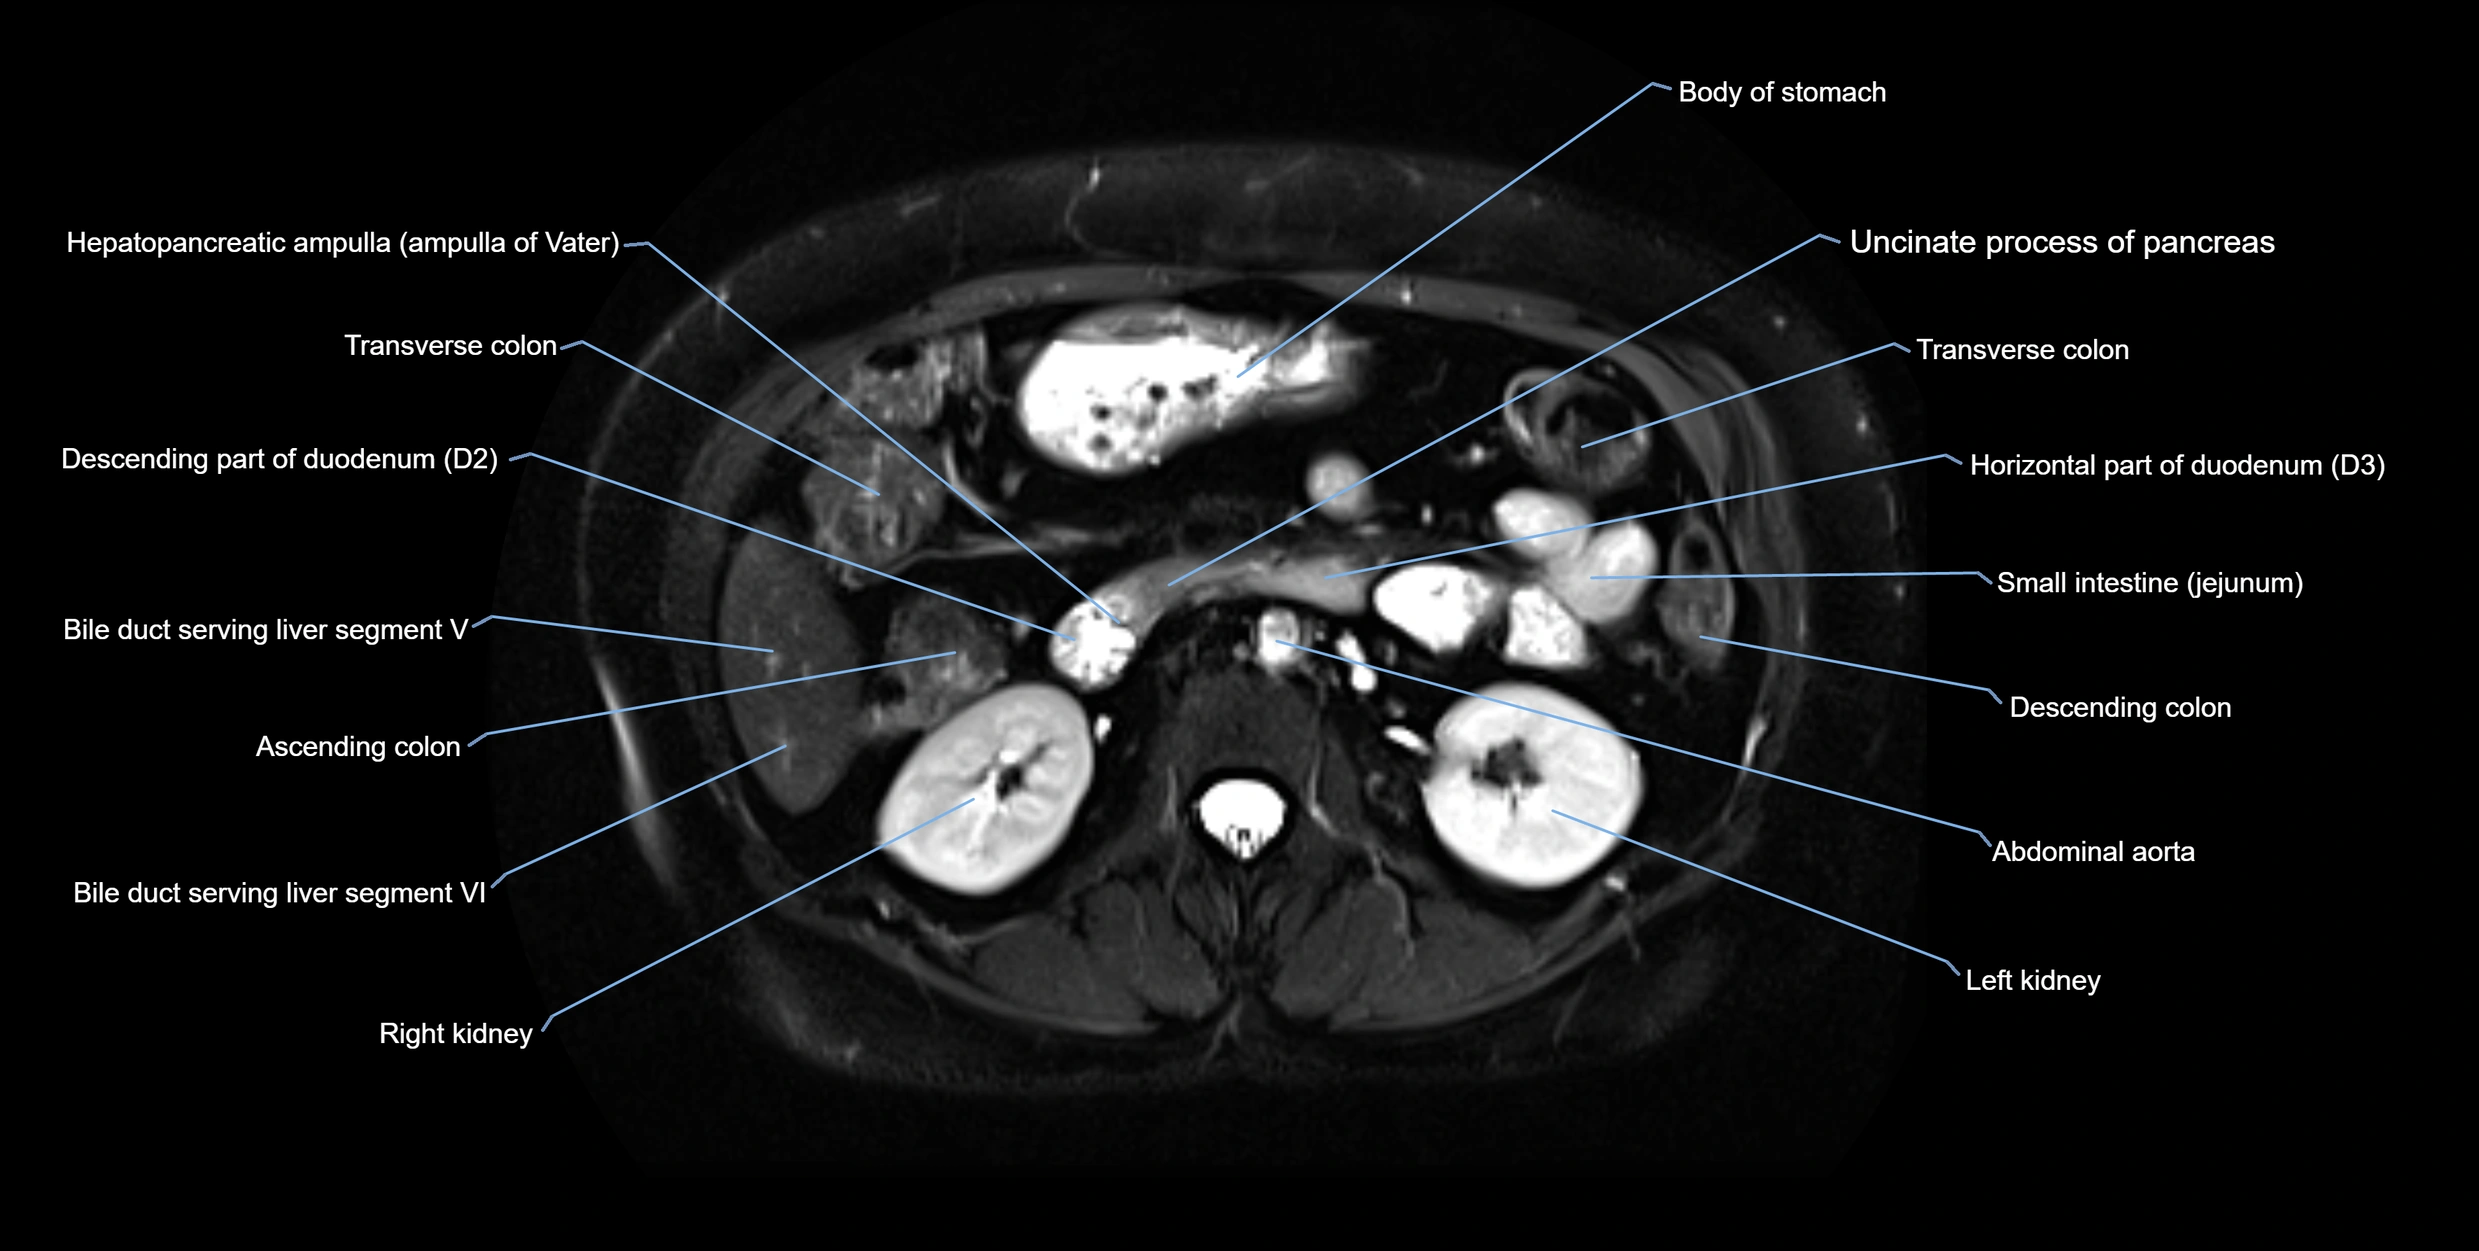

T2-weighted images:

• Duct fluid appears bright

• Accessory duct seen as a fine high-signal tubular structure in pancreatic head

T2 Fat-Saturated HASTE (single-shot):

• Accessory duct: bright, thin linear structure in pancreatic head

• Stones, strictures, or air bubbles appear as dark filling defects

• Excellent for rapid evaluation of duct patency

MRI image

image